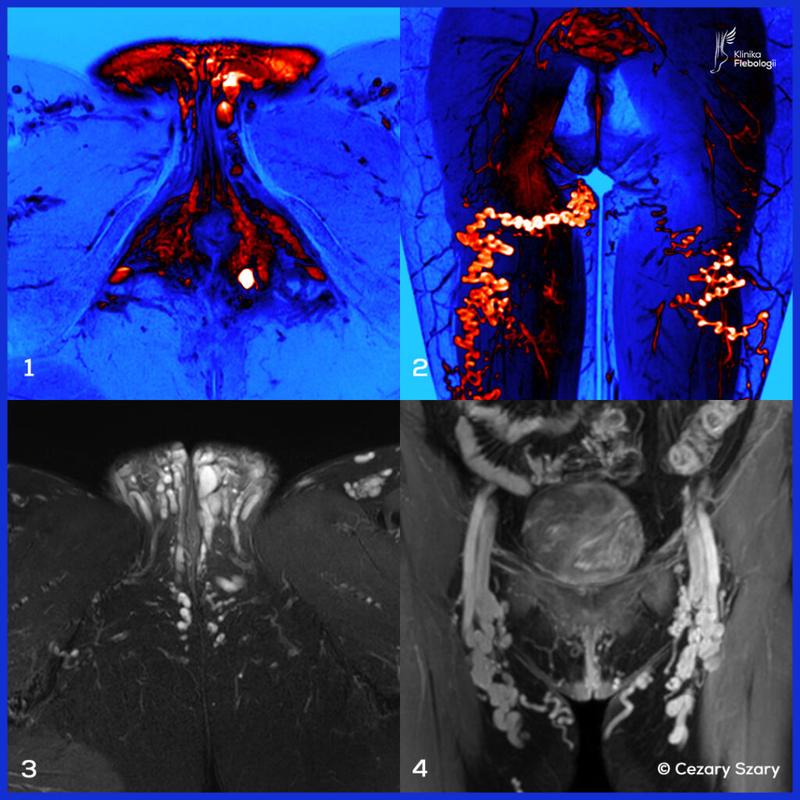

1. Diagnostyka: Zanim przystąpisz do jakiejkolwiek interwencji, konieczne będzie wykonanie diagnostyki. Proces ten obejmuje badanie fizykalne, które pomoże ocenić stan naczyń żylnych. Lekarz często zaleca USG Doppler, aby sprawdzić przepływ krwi w żyłach sromu. Ponadto, w celu zlokalizowania potencjalnych problemów z krążeniem, mogą być potrzebne dodatkowe badania, takie jak angio-CT czy flebografia. Odpowiednia diagnostyka pozwoli lekarzowi dobrać najbardziej skuteczną metodę leczenia.